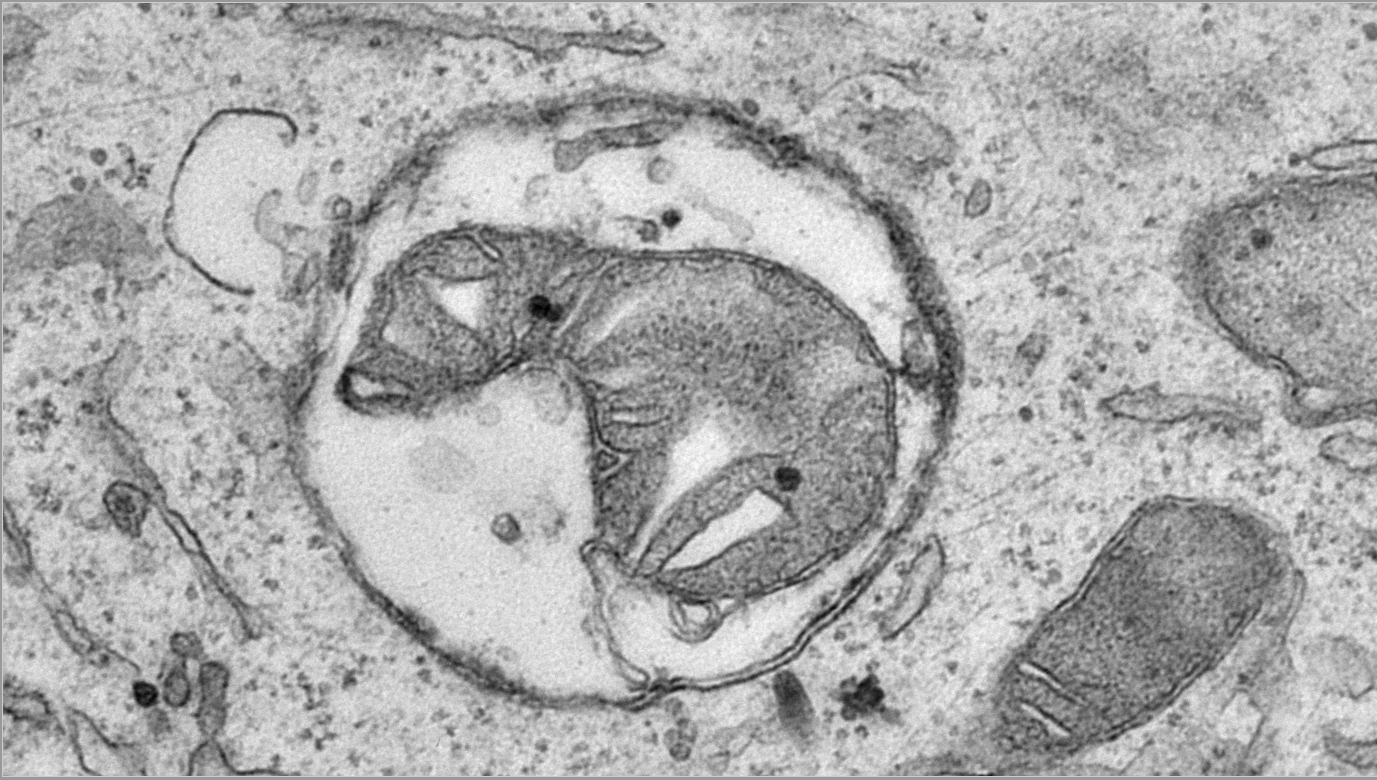

This electron microscopy image depicts a mitochondrial remnant in an autophagosome (a double-membrane vesicle that forms around cellular material that needs to be removed). It represents a key defect in the degradation of mitochondria as a major finding of the paper.

Zoë Van Acker, first author of the study: “It is exciting to now have answers to these questions, starting with identifying that most of the DNA actually comes from mitochondria, or the neuron’s powerhouses. Mitochondria have a rapid turn-over in the energy-consuming neurons, and ‘used up’ mitochondria need to be recycled through lysosomes and replaced by young ones. However, when PLD3 is defective, the DNA from mitochondria fails to become degraded in lysosomes and accumulates. This clearly triggers a chain of events that results in a clogging of the lysosomal system.”

The research team found that the excess mitochondrial DNA leaks out of lysosomes, similar to an oil leak. This leak causes neurons to activate certain signaling pathways, such as the cGAS-STING pathway. Unfortunately, instead of stopping this leak, STING activation unintentionally makes the problem worse. It adds more waste and cell components to the overwhelmed lysosomes, which cannot handle the increased load. As a result, the lysosomes fail to break down their usual waste, including toxic substances like amyloid peptides and other toxic fragments of the amyloid precursor protein, which are known to harm neurons and contribute to the development of amyloid plaques associated with Alzheimer’s disease. This accumulation of toxic substances further damages the neurons and may therefore contribute to the worsening of the pathology.